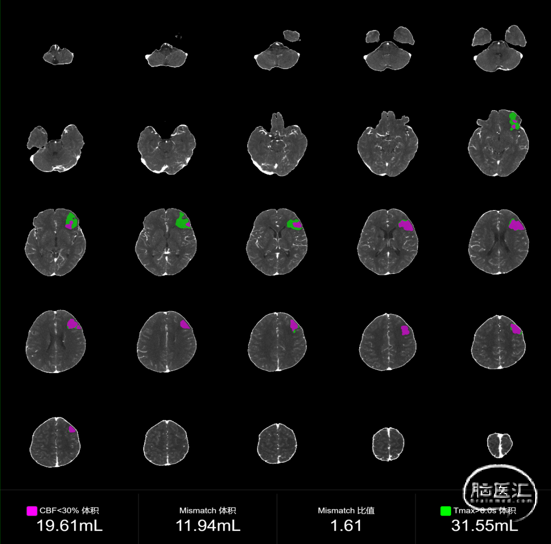

急诊颅脑CTP:

左侧额叶、枕顶叶脑梗塞,全脑核心梗死区(CBF<30%)体积为19.61mL,低灌注区(Tmax>6.0s)体积为 31.55mL,Mismatch体积为11.94mL,Mismatch比值为1.61。